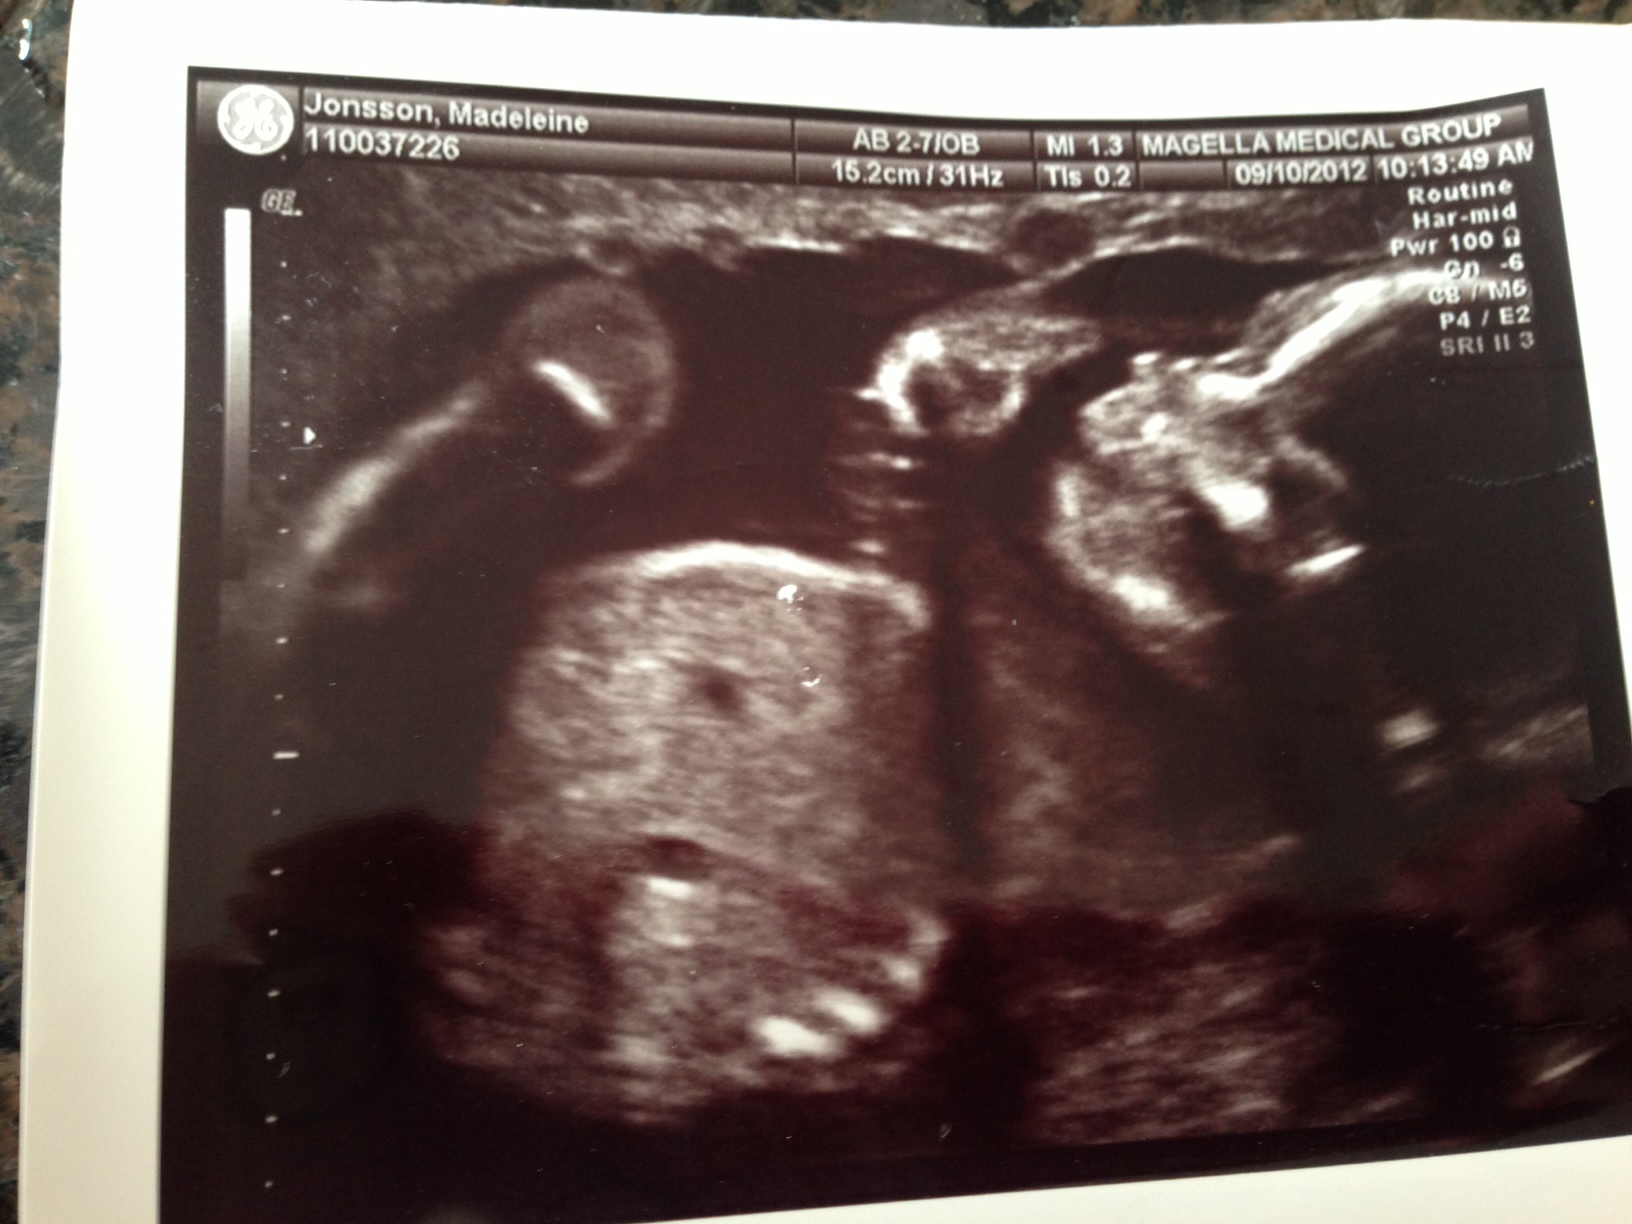

ringde dom idag på morronen och sa att jag ville komma in på non stress test för att

kolla hur bebisen mår i magen. Fick komma dit vid 10 och dom gjorde UL för att mäta

vattnet och sedan sitta med sladdar på magen för att kolla hjärtljud och allt sånt.